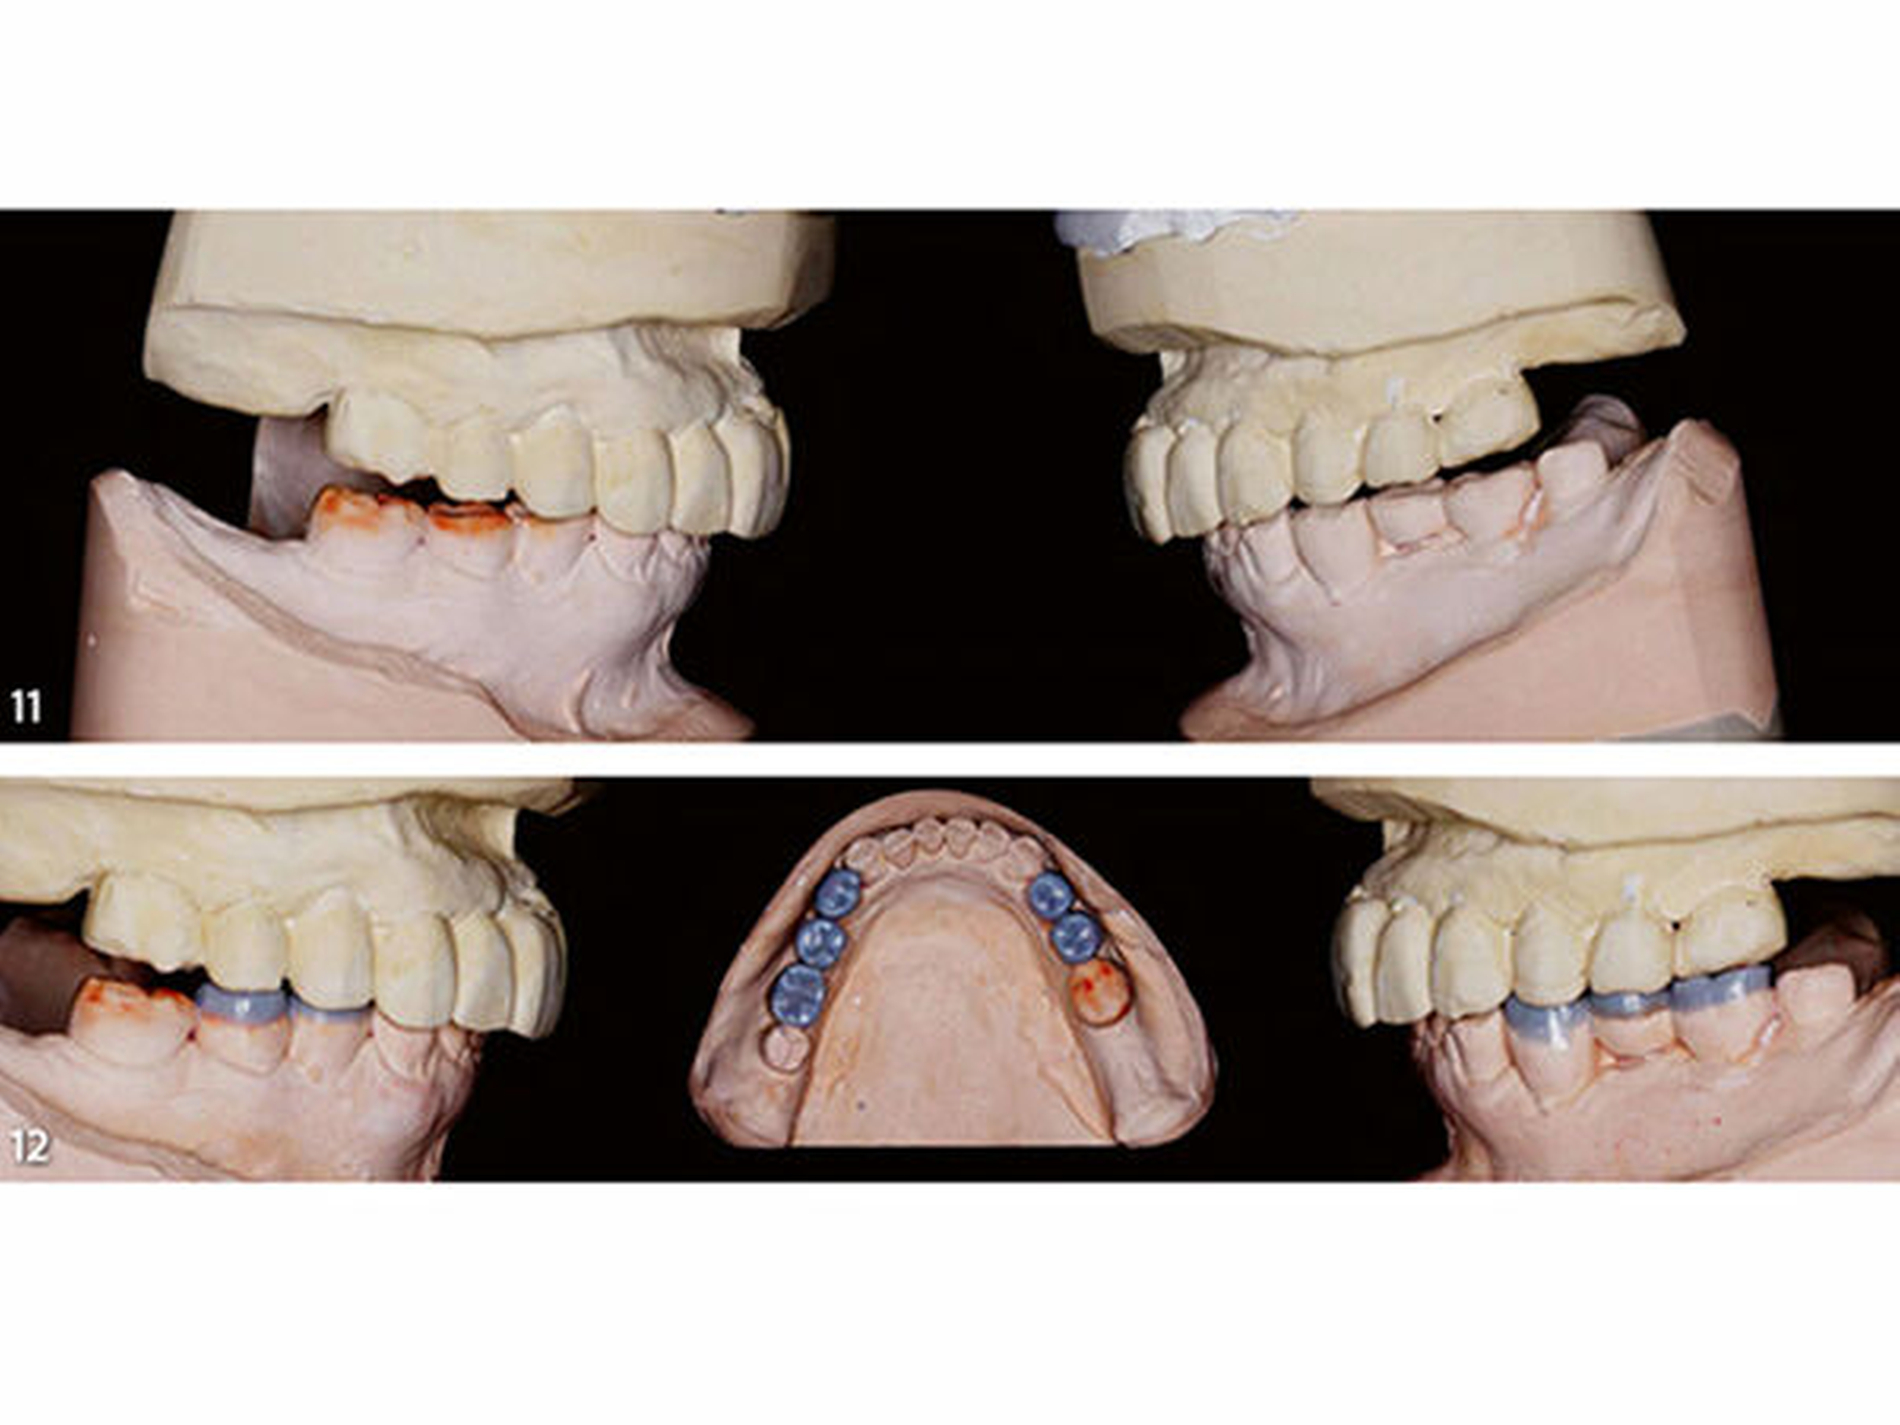

Dritte Laborphase: Nach der komplikationsfreien Evaluation der therapeutischen horizontalen und vertikalen Bisslage an der Patientin wurde das Unterkiefermodell im zahntechnischen Labor mithilfe der Okklusionsschiene neu einartikuliert (Abb.11). Es wurde anschließend ein segmentweises Wax-up der idealen Okklusion erstellt (Bartlett 2016; Muts et al. 2014). Im ersten Schritt des Wax-up erfolgte die Rekonstruktion der okklusalen Anteile der Seitenzähne bis auf die endständigen Zähne beiderseits (Abb.12). Dadurch kann die nachfolgend angefertigte erste Übertragungsschiene später im Mund an den letzten Zähnen der Zahnreihe und im Frontzahnbereich definiert abgestützt werden (Schmidlin et al. 2009c). Der teilaufgewachste Unterkiefer wurde mit feinzeichnendem Silikon dupliert und auf diesem Gipsmodell eine Hilfsschiene in der Tiefziehtechnik (Schiene1) für die intraorale Übertragung des Wax-up mit Komposit angefertigt (Abb.13). Diese als Formträger verwendete Schiene wird aus einer Polyethylenfolie (Copyplast, Scheu Dental) tiefgezogen, die sich nicht mit Acrylaten verbindet, um sich von den damit eingebrachten Kompositaufbauten intraoral problemlos wieder abnehmen zu lassen.